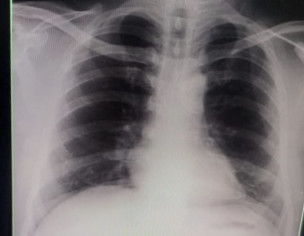

My brother is covid positive. He is diabetic too. He is having sore throat and body ache now. The attached photo is his chest X-ray. Can you please tell what’s his state now.

Chest d rat show inflamation in lungs consult online for detailed assessment